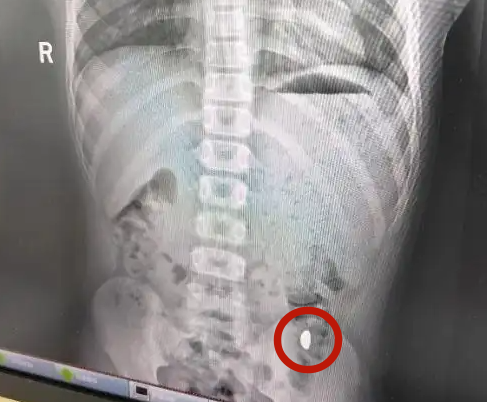

The foreign object reportedly found in the boy's body.

Image via Weibo via Sin Chew DailyGold beans are small ingots with a bean-like shape and are popular among China's youth

A diagnosis revealed a foreign object in his body, and he passed the gold the same day he went to the hospital.